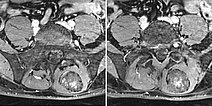

In dynamic contrast-enhanced MR angiography (late phase over 2 min after contrast administration, left coronal and right sagittal), the lesion shows no contrast enhancement or increased vascularization. It is practically invisible.

In the axial, fat-saturated T1-weighted images after contrast medium administration, an initially inhomogeneous accumulation of contrast medium in terms of contrast pooling occurs only slowly and incompletely. This is also relatively typical of a venous malformation.